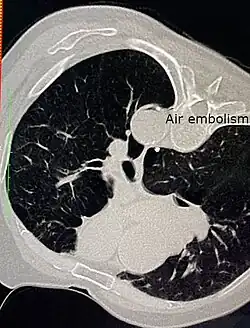

Air embolism in the descending thoracic aorta after CT guided percutaneous lung biopsy of a suspected lung tumour.